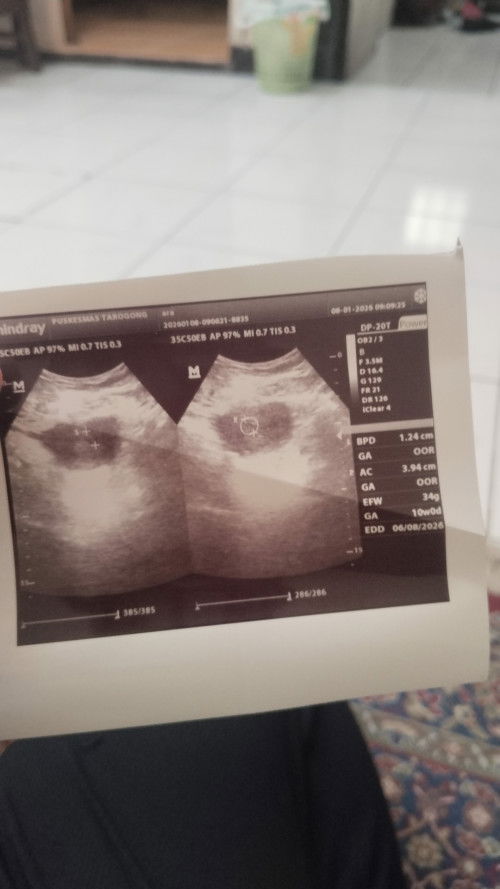

Bismillah ada yang sma ga yah seperti saya kasus nyaa... Saya terkahir Haid itu 22 November dn masa subur saya itu di 2Desember lalu saya Tespek ternyata hasil nya garis nya 2 tapi yg 1 samar saya coba Tespek sudah 3x dan hasil nya masih samar... Dan ternyata pas saya ke dokter kata bidan usia kandungan saya sudh 7minggu . Tetapi baru kelihatan kantung nya saja dan itu pun di bawah. Apakah ada yang sama sperti saya? 🙏🙏dan yang saya rasakan seperti tidak hamil krna blum ada tanda"mual dll yg saya rasakan 🙏🙏🙏#mohonbantujawabbunda #Sharingdong_Bund #firstmom #sharing